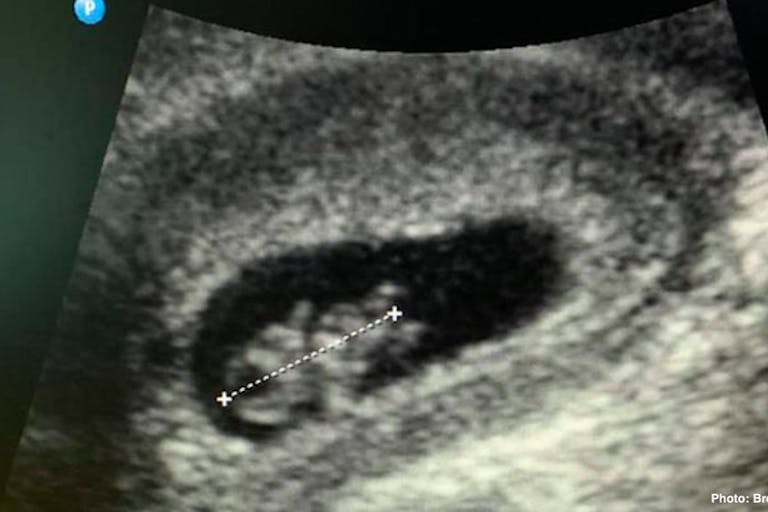

Dr. Brent Boles, the medical advisor for Abortion Pill Rescue, took to Facebook on Friday to share images of a preborn baby whom he helped save from the effects of the abortion pill.

“I have this patient’s permission to use these ultrasound images,” he wrote. “One week ago, she took Mifeprex, the first medication used in the all-too-common medication/chemical abortion process. She was 7 1/2 weeks along. She was already in tears by the time she left the building. She encountered someone who knew that reversal of the process could be attempted, and through that process was able to get the prescription to begin the reversal process.”

After beginning progesterone shots, the woman met with Boles a week later. Her baby, then 8 1/2 weeks, had a normal heart rate, and his head, chest, and arm and leg buds are visible in the ultrasound images. “The baby was active and moving,” said Boles, “and the mother was incredibly relieved.”